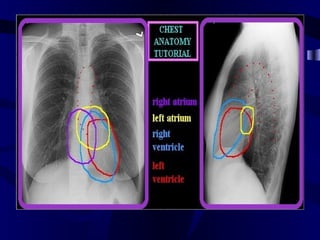

CT Coronal Reconstruction RightBrachiocephalic Left Brachiocephalic Vein Vein Superior Vena Cava Right Atrium Inferior Vena Cava